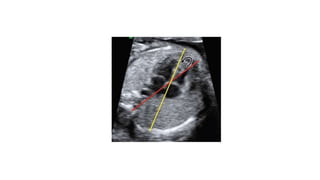

• #18 The axis of the fetal heart can be determined by drawing two imaginary lines. One passing through the anterior chest wall and the spine (red) and another passing through the interventricular septum (yellow). The normal cardiac axis is between 25–65°

• #19 Cardiac size can be determined by calculating the cardiothoracic ratio. It is the ratio of the area covered by the heart (red) to the entire thoracic area (yellow)